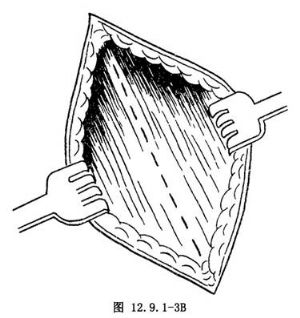

有人主張做橫行皮膚切口有利癒合,其做法是經過麥克伯尼點做橫切口,切口的2/3在該點外側,切口避開髂前上棘。以上兩種切口寧稍偏高,有利於闌尾的顯露及操作。皮膚、皮下組織切開後,按腹外斜肌方向切開腹外斜肌腱膜(圖12.9.1-3B),用血管鉗交替分開腹內斜肌及腹橫肌纖維,顯露腹膜(圖12.9.1-3C)。用血管鉗交替夾提並切開腹膜,避免誤傷腸管。腹膜切口方向斜行、橫行均可。